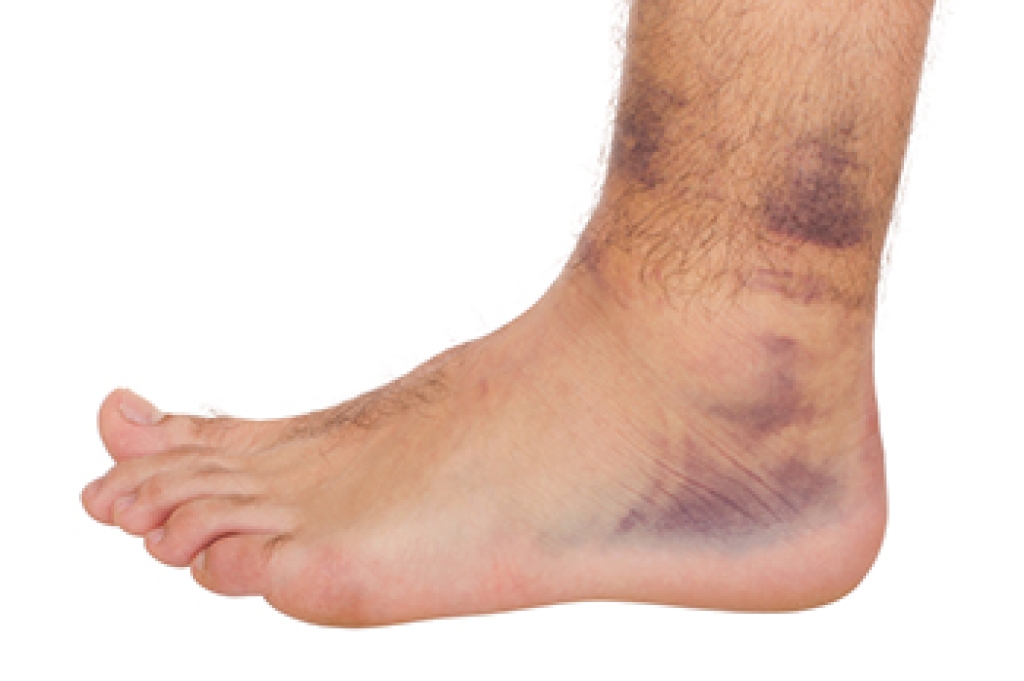

Falls among seniors are a significant concern, often resulting from a combination of factors. Common causes include muscle weakness, poor balance, vision problems, and environmental hazards like clutter or uneven floors. Medication side effects and medical conditions such as arthritis can also contribute to fall risk. To prevent falls, it is important to implement several practical strategies. Ensure the home environment is safe by removing trip hazards, installing grab bars, and improving lighting. Encourage regular exercise to enhance strength and balance like walking or specialized fall prevention classes. Regular eye exams and reviewing medications can also help address underlying issues. If you have injured your foot or ankle from falling, it is suggested that you consult a podiatrist who can treat various conditions.

Falling can be a traumatic and embarrassing experience for elderly persons; this can make them less willing to leave the house, and less willing to talk to someone about their fears of falling. Doing such things, however, will increase the likelihood of tripping or losing one’s balance. Knowing the causes of falling and how to prevent them is the best way to mitigate the risk of serious injury.